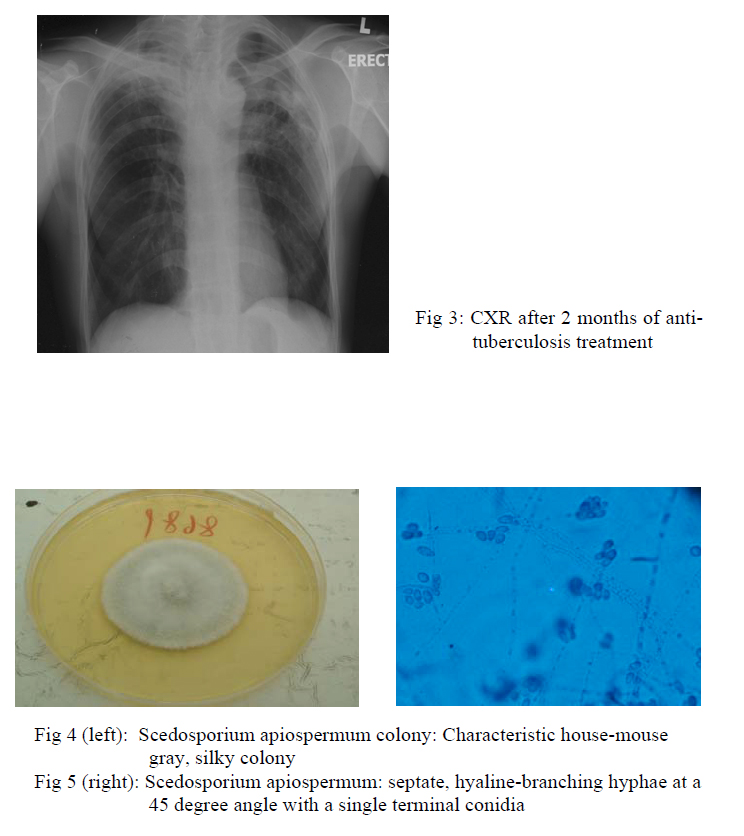

Chest radiograph taken after 2 months of treatment showed resolved right upper lobe consolidation, fibrotic change of right upper lobe and the left upper lobe nodule was static in size (fig 3). However, sputum for fungal culture grew scedosporium apiospermum (fig 4,5). Flexible bronchoscopy was repeated and AFB smear and fungal culture were negative in bronchoalveolar lavage. Computed-tomography (CT) guided fine needle aspiration showed degenerated hyphae only. Patient still experienced haemoptysis intermittently but there was no sign of other organ involvement. Voriconazole was not started in view of localized disease and potential drug interaction with rifampicin.

Scedosporium infection is increasingly recognized as a cause of infection in severely ill or immunocompromised patients1. Scedosporium apiosperum and Scedosporium prolificans are the two major human pathogens. Scedosporium apiospermum is the asexual form of Pseudallescheria boydii. It can be found in soil, sewage and polluted water. Diagnosis of an invasive mould infection may be made when septate, hyaline-branching hyphae at a 45 degree angle with a single terminal conidia, is identified in a bed of inflammation (fig 5). Aspergillus or fusarium infection also have similar microscopy appearance and a definitive diagnosis can be made by culture. It cause a wide range of pulmonary manisfestations, from simple colonization to mycetoma formation and invasive disease, very similar to that caused by Aspergilllus spp1,2. Coinfection with tuberculosis and scedosporium has been reported3,4. There was no microbiological evidence of tuberculosis infection in this case but the radiological improvement after anti-tuberculosis treatment suggested underlying infliximab related pulmonary tuberculosis coinfection. Treatment option and duration for scedosporium apiospermum have not been established. It is resistant to commonly used antifungal such as amphotericin B and fluconazole whereas voriconazole has the greatest efficacy against the organism5,6. In our case, there was concern that concurrent administration of rifampicin would decrease the serum level of voriconazole. Treatment failure is common in Scedosporium infection and surgical debridement is encouraged as it is associated with better outcome7.